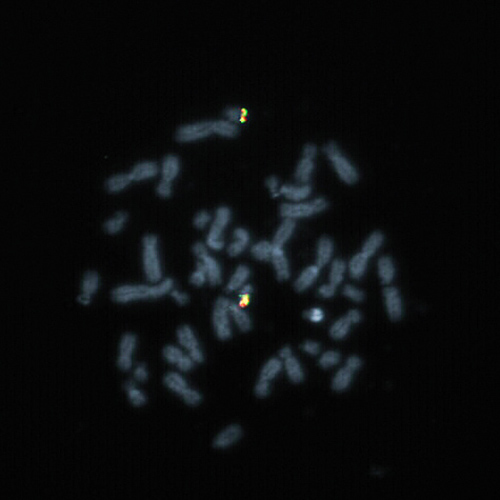

BCL2 (18q21) Break probe hybridized to a normal metaphase.

Follicular lymphoma is a mature B-cell lymphoma characterized by the presence of the t(14;18) translocation that juxtaposes the BCL2 locus on chromosome 18q21 to the immunoglobulin H (IGH) locus on chromosome 14q32, resulting in the overexpression of the anti-apoptotic protein BCL2. Next to IGH, other translocation partners to BCL2 are also known (e.g. IGK at 2p11.2 and IGL at 22q11). A break or split assay is therefore best suited to detect rearrangements of the BCL2 gene region at 18q21. The BCL2 (18q21) Break FISH probe is optimized to detect translocations involving the BCL2 gene region at 18q21 in a dual-color, split assay on metaphase/interphase spreads, bloodsmears and bone marrow cells.